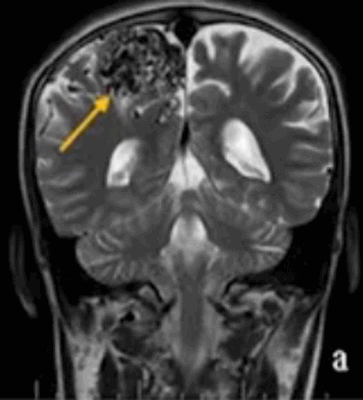

![Артерио-венозная мальформация на МРТ головного мозга]()

Артерио-венозная мальформация на МРТ головного мозга (указана стрелкой)